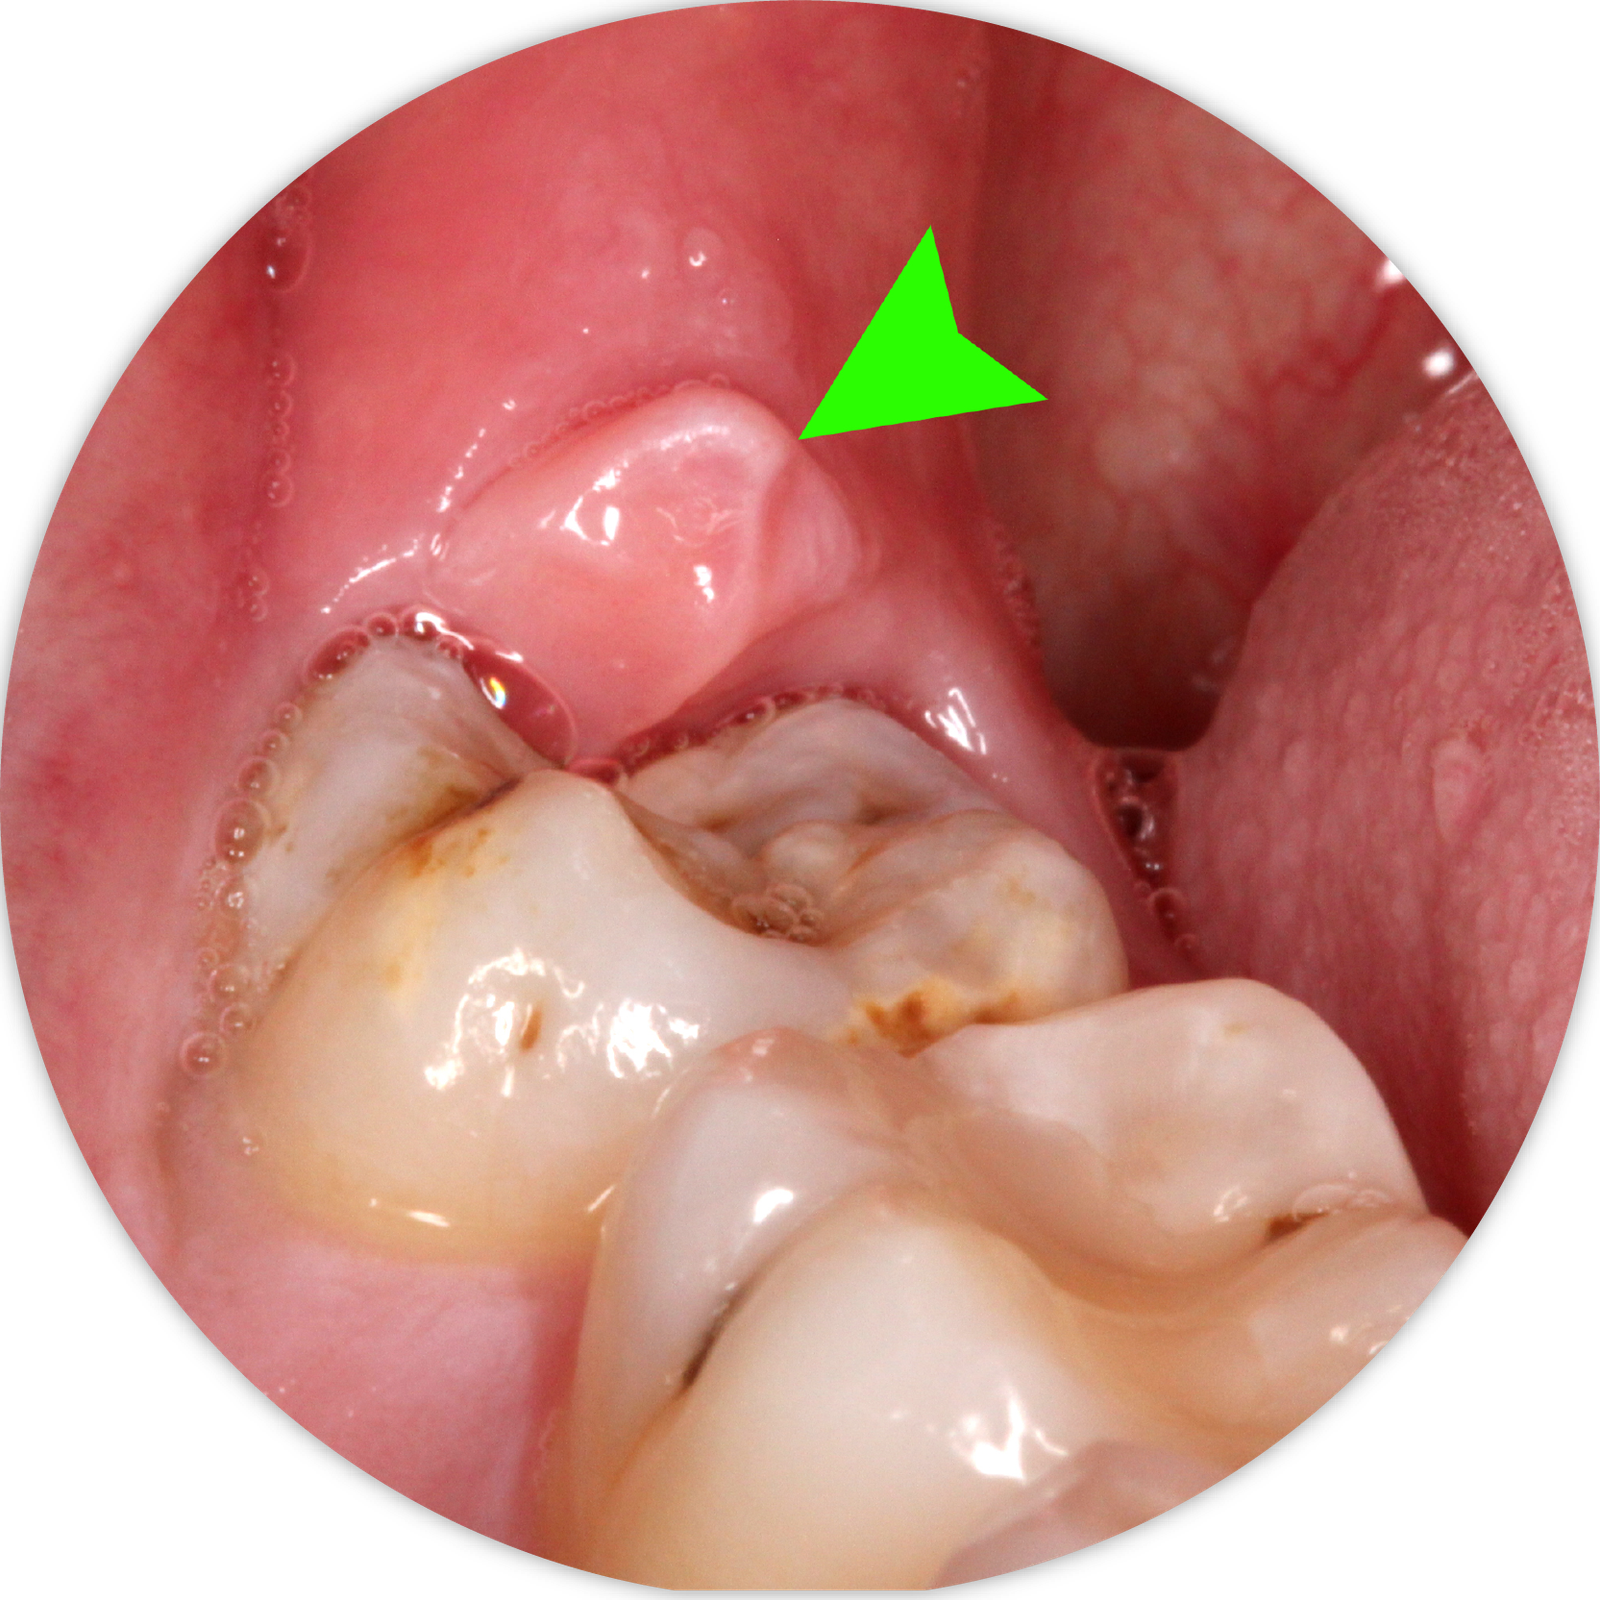

Răng khôn hay còn gọi là răng số 8, là những chiếc răng mọc ở phía trong cùng hai hàm răng ở những người trưởng thành trong độ tuổi trung bình từ 17- 25. Vì cấu trúc xương hàm người Việt chúng ta thường nhỏ, răng khôn không có đủ chỗ để mọc thẳng, dẫn đến tình trạng mọc lệch, mọc 1 phần, đâm xiên vào răng bên cạnh. Điều này dẫn đến nguy cơ kẹt thức ăn, viêm nướu, sâu răng, áp xe hoặc thậm chí là sưng viêm 1 bên mặt. Chúng tôi khuyến nghị khách hàng nên đi nhổ răng khôn từ giai đoạn răng mới mọc nhằm tránh các biến chứng và cơn đau.

Răng khôn có thể được nhổ trước hoặc sau khi thấy răng này mọc trên cung hàm. Trước khi mọc trên cung hàm, vị trí răng khôn được thể hiện trên phim X-quang toàn cảnh. Bác sĩ sẽ chỉ định nhổ răng khôn nếu tiên đoán răng sẽ mọc kẹt, mọc lệch, có nguy cơ gây biến chứng. Sau khi thấy răng khôn đã nhú hoặc mọc, khách hàng có thể đến thăm khám và nhổ răng khôn. Việc nhổ răng nên được tiến hành trước khi vùng răng này bị viêm sưng. Nếu có tình trạng đau, sưng và viêm, bác sĩ sẽ kê toa thuốc trước khi tiến hành nhổ răng.